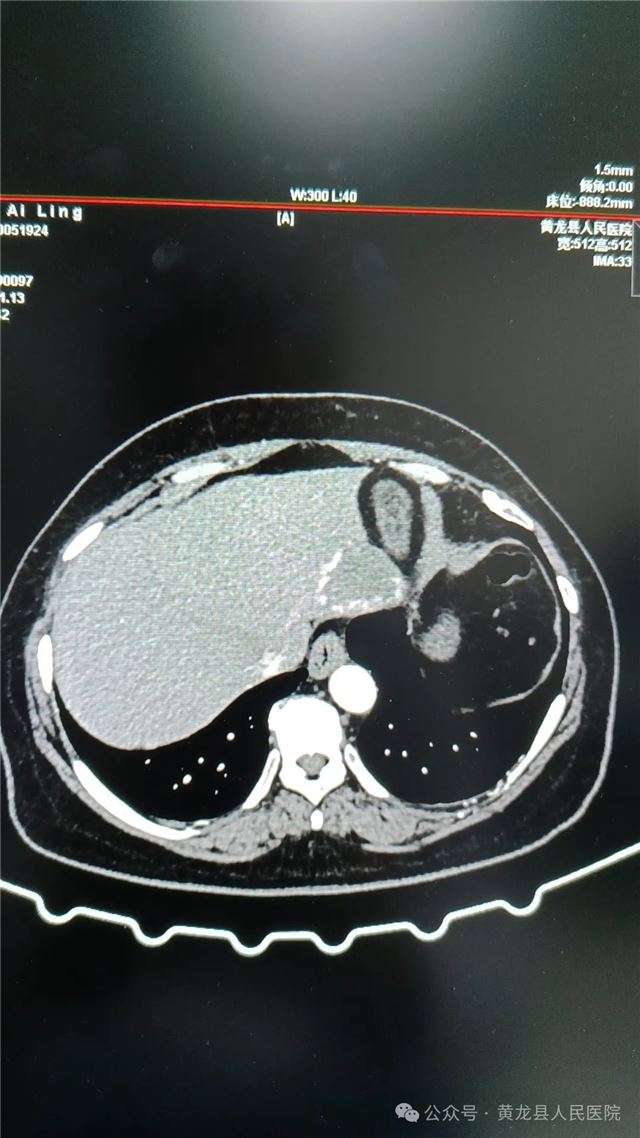

1,术前上腹部CT(平扫、增强)

患者女,58岁,在体检时发现肝占位性病变,经进一步检查后确诊“肝血管瘤”。